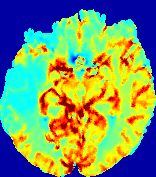

4.3.2 Diffusion Imaging via Advection-Diffusion

Slice #1Slice #2Slice #3Slice #4Slice #5Slice #6Dgtsuperscript𝐷gtD^{\text{gt}}Refer to captionRefer to captionRefer to captionRefer to captionRefer to captionRefer to captionDestsuperscript𝐷estD^{\text{est}}Refer to captionRefer to captionRefer to captionRefer to captionRefer to captionRefer to captionRefer to caption0.300.300.300.240.240.240.180.180.180.120.120.120.060.060.060.000.000.00(mm2/s)𝑚superscript𝑚2𝑠(mm^{2}/s)𝐕est𝟐subscriptnormsuperscript𝐕est2\|\bf{V}^{\text{est}}\|_{2}Refer to captionRefer to captionRefer to captionRefer to captionRefer to captionRefer to captionRefer to caption0.00300.00300.00300.00240.00240.00240.00180.00180.00180.00120.00120.00120.00060.00060.00060.00000.00000.0000(mm/s)𝑚𝑚𝑠(mm/s)

Figure 15: PIANO identifiability testing: diffusion imaging via advection-diffusion. Top row shows Dgtsuperscript𝐷gtD^{\text{gt}} used for simulating ground truth pure diffusion. Rows below show the estimated Destsuperscript𝐷estD^{\text{est}} and 𝐕est2subscriptnormsuperscript𝐕est2\|{\bf{V}}^{\text{est}}\|_{2} on corresponding slices. Note that the plotted value scale for 𝐕est2subscriptnormsuperscript𝐕est2\|{\bf{V}}^{\text{est}}\|_{2} is 0.01 of that for Dgtsuperscript𝐷gtD^{\text{gt}} and Destsuperscript𝐷estD^{\text{est}}.

Similarly, we test the behavior of PIANO when estimating both advection and diffusion from a pure diffusion-driven process. The goal is to determine if PIANO is able to recognize that there is only diffusion governing the given concentration time-series. We use the same ‘Diffusion Imaging’ data simulation of Sec. 4.2.1 as the concentration dataset, PIANO estimates both velocity 𝐕estsuperscript𝐕est{\bf{V}}^{\text{est}} and diffusivity Destsuperscript𝐷estD^{\text{est}}. Estimation results in Fig. 15 confirm PIANO’s identifiability again: the estimated 𝐕est2subscriptnormsuperscript𝐕est2\|{\bf{V}}^{\text{est}}\|_{2} is almost invisible compared to Destsuperscript𝐷estD^{\text{est}}, even plotted with a 1%percent11\% value range compared to that for Destsuperscript𝐷estD^{\text{est}}. On the other hand, Destsuperscript𝐷estD^{\text{est}} achieves comparable estimation performance as ‘Diffusion Imaging via Diffusion’ in which PIANO predicts Destsuperscript𝐷estD^{\text{est}} alone (shown in Fig. 13).